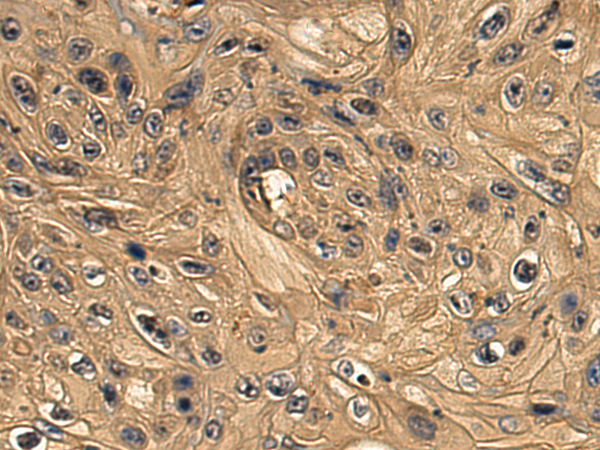

分类: 科研抗体货号: P08917别名: HCC-8应用: WB,IHC反应种属: Human, Mouse